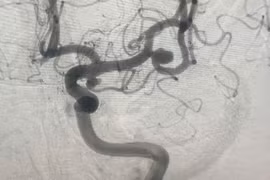

Phương pháp điều trị phình mạch máu não hiệu quả, tránh vỡ gây tử vong

Phình mạch máu não là căn bệnh tiềm tàng nguy hiểm, nếu không được phát hiện và điều trị, khi vỡ sẽ rất nguy hiểm, để lại nhiều biến chứng nặng nề, thậm chí là tử vong.